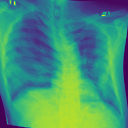

Additionally, we evaluate the performance of DiffeoNN on real-world data, using a dataset with chest X-ray images and their ground-truth lung segmentation from (RSUA, 2023). The original dataset contains images and corresponding ground-truth segmentations into three different classes (“Non-Covid”, “Covid”, and “Non-Covid-Pneumonia”). We combine the images and corresponding ground-truth segmentations of the initial three classes into one dataset, which is then split into a training dataset of image-segmentation pairs, a validation dataset of pairs, and a test dataset of pairs. We then proceed as in Section 4.1.1 to create a dataset of diffeomorphically transformed images.

We apply DiffeoNN, the inner U-Net (naïve approach) and an augmented U-Net, which is trained on the original and the diffeomorphically transformed training dataset, to the diffeomorphically transformed images from the test dataset. Visual results are presented in Figure 4 and further details on the experimental setup, training, and additional examples in Appendix B. The results closely mirror those obtained on the synthetic dataset, see Table 1(b). On average, DiffeoNN outperforms the naïve approach, validating the effectiveness of our approach. The canonicalisation step pushes the input image towards the training dataset by moving the thorax to a more central position and aligning the shoulders, which makes it easier for the inner U-Net to predict an accurate lung segmentation. While our method performs slightly below the augmented gold-standard baseline, it offers more flexibility by not relying on data augmentation or retraining, making it a practical and robust solution in real-world applications.

| Input | Canonicalised Input | Segmentation of | Output DiffeoNN | Output Naïve U-Net | Output Augmented U-Net | Ground-Truth Segmentation |